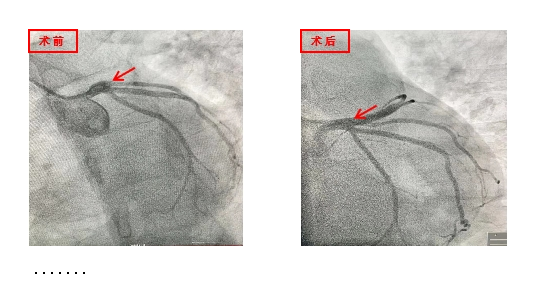

11月13日,90后的小师,8小时前突然出现胃痛,同时伴随有恶心呕吐,可自行缓解,未予重视,后症状呈持续性,至我院就诊,诊断后急性下壁ST段抬高型心肌梗死,给予药物治疗及支架植入后好转出院。